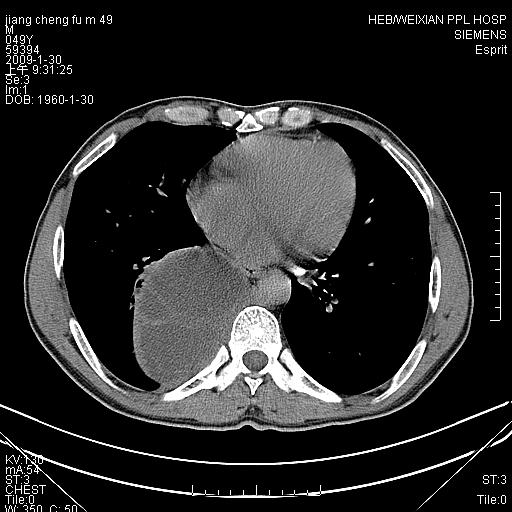

男性,49岁,主因胸痛,右肺呼吸音低。胸片提示肺占位

考虑右侧脊柱旁沟囊性病变。1:支气管囊肿或食管囊;2:神经源性肿瘤。

右后纵隔囊性占位;考虑为:1)淋巴管囊肿。2)食管囊肿。建议:进一步检查。

右后纵隔囊性占位,建议先做增强,后做穿刺活检。

在分析这个病变时,首先病灶边界清晰,但其内密度不均匀,有条索状状实性成分,肿块的外侧壁亦呈一不均匀的厚壁改变,因此支气管囊肿的可能性不大。主要考虑神经源性肿瘤(主要考虑神经鞘瘤,因为它囊变的机率比较高),其次考虑肺膈离征,行增强扫描如发现来自胸主动脉供血动脉血管可确诊。

考虑右侧脊柱旁沟囊性病变,囊骨有分隔,囊壁较厚。1:神经源性肿瘤;2:食管囊肿或淋巴管囊肿。支持!

囊状肿块内有线样软组织分隔,支气管囊肿及食管囊肿可不考虑。我考虑:1、囊性肺膈离征(需要增强扫描来排除)。2、神经鞘瘤。3、淋巴管囊肿。